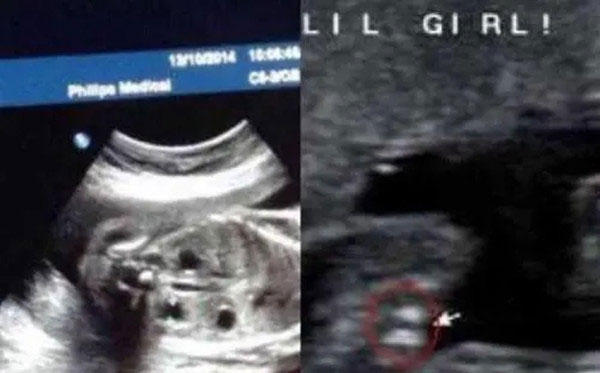

女宝b超三条线是哪三条 女宝宝b超图解

如上图所示,怀孕四个月左右,男胎儿女胎儿的生殖器官已经分化明显。通过b超可以清晰地可看出不同,女宝宝两腿中间是三条白线,这是女孩最明显的标志。

而男胎儿,两腿中间没有三条白线。男胎儿最明显的标志就是小突起,类似于小jj的东西突出来。

@网妈说:女宝B超图中有三条线,男娃是没有的;B超图中有小突起,一般都是男孩,这一点技术好的医生是不会看错的。